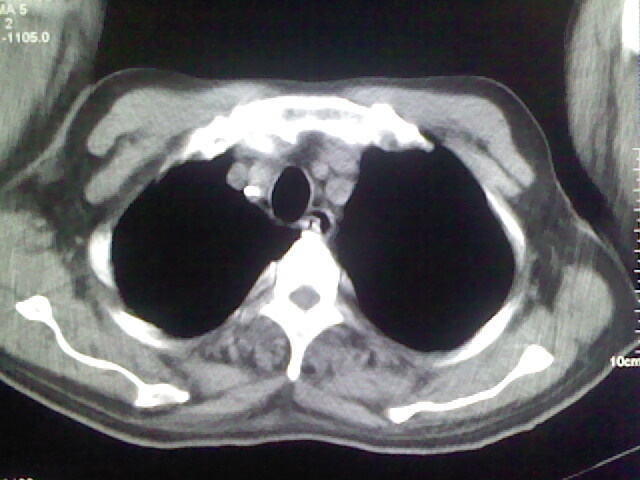

男,70岁,脑出血,长期卧床,左侧背部可触及肿块

慢性间质性炎症,与老年患者长期卧床相关,胸壁软组织及肋骨未见异常。

背部没见到肿块呀,有感染灶。

肺部感染,背部筋膜增厚,考虑坠积性水肿或炎症